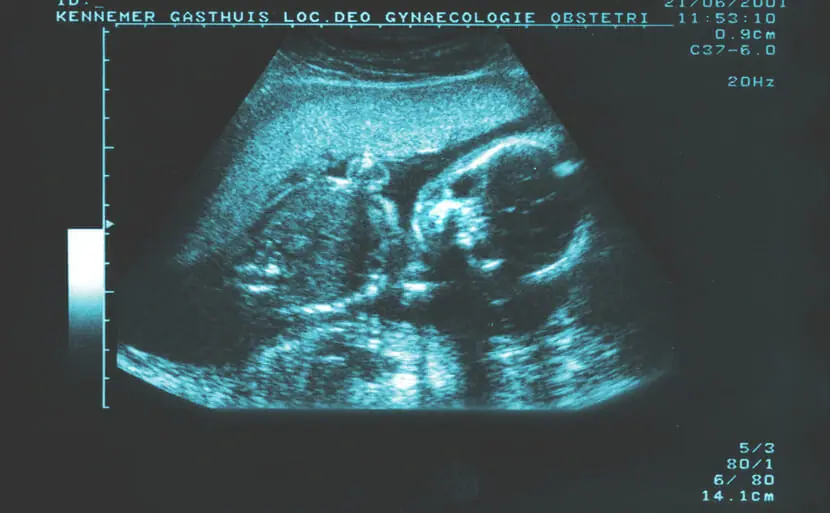

エコーで21トリソミー(ダウン症)が分かる場合もあります

妊娠中に行うエコー検査(超音波検査)で21トリソミー(ダウン症)の胎児の特徴を発見できる場合があります。21トリソミー(ダウン症)の胎児は血流が悪いため、首の後ろにむくみが出ることが多いためです。このむくみをNT(Nuchal Translucency)といい、通常妊娠11週から13週に計測することができます。

首の後ろのむくみ以外にも特有の特徴があります。

顔に見られる特徴の一つは鼻です。鼻の骨がない、鼻の骨が薄い、鼻の骨の成長に遅れがあるなどの特徴が見られます。

また、体の特徴では、手足の長さが基準より短い、心臓の病気がある(三尖弁逆流・静脈管逆流)、頭が大きいなどの所見があると、21トリソミー(ダウン症)の胎児である可能性があります。

顔や体の特徴を細かく見ていく必要があるので、通常の妊婦検診で用いられる2Dエコーよりも、4Dエコーの方が、発見しやすいと言えます。心配な場合は、4Dエコーが見られる産院でみてもらうと良いでしょう。

エコーで21トリソミー(ダウン症)が分かる確率

エコーによって、21トリソミー(ダウン症)の特徴を発見できることは多いですが、胎児の位置などによっては明確にわからないこともあります。また、所見があっても21トリソミー(ダウン症)によるものではないこともあります。そのため、どのくらいの確率で21トリソミー(ダウン症)がわかるとは定義することはできません。

エコーで21トリソミー(ダウン症)が分かる時期はいつ(何週目)?

エコーで21トリソミー(ダウン症)の所見が観察できるようになるのは、おおむね妊娠11週以降です。